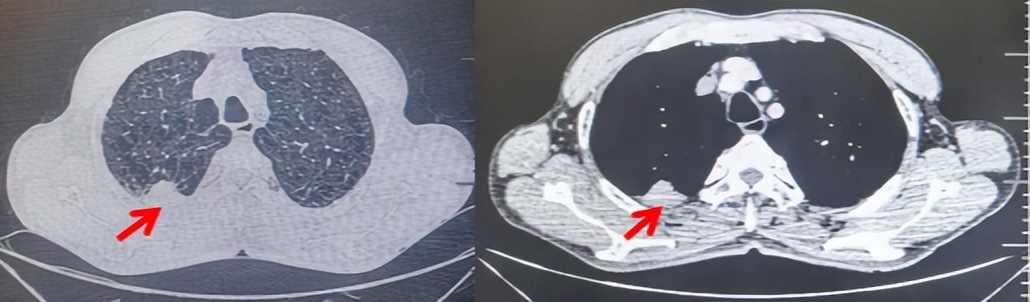

69岁男性,无糖尿病、高血压、心脏病等基础疾病,无吸烟、饮酒史,无肿瘤家族史。2023.06.07行胸部CT检查:右肺上叶胸膜下见肿物影,大小约33mm×22mm,边缘可见分叶,考虑恶性病变可能性大,双肺间质改变(如图1)。2023.06.14行“单孔胸腔镜下右肺上叶切除、肺门及纵隔淋巴结清扫、胸膜粘连松解术”;术后病理:(右肺上叶)腺癌(低分化,实体型占60%,不良腺体占40%),局灶伴神经内分泌标记表达(CD56、Syn),可见STAS及胸膜侵犯,未见确切神经侵犯及脉管内癌栓;(气管切缘)净;(淋巴结)未见转移癌0/26(2组0/2;4组0/6;7组0/2;对侧7组0/8;10组0/2;11组0/3;12组0/2;13组0/1)。术后分期pT2aN0M0 IB期,术后NGS基因检测:无驱动基因突变,PD-L1(22C3)TPS<1%。术后定期复查。

图1:患者手术前(2023.06)胸部CT肺窗及纵隔窗

图2:患者胸膜及肋骨转移(2024.11)胸部CT肺窗、纵隔窗及骨窗